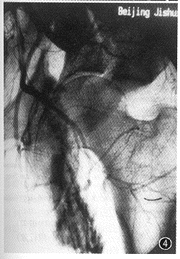

图3,4 男,43岁,车祸致骨盆骨折12 h。图3为左髂外动脉造影,见动脉中断、断端呈锥状。图4示髂外动脉断端内对比剂向左股内侧弥散,髂内动脉造影示股动脉依靠侧支循环供血。诊断为髂外动脉断裂,血栓形成,股动脉侧支循环建立